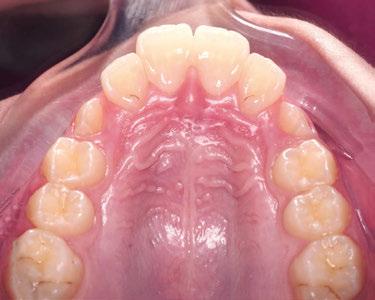

Figuras 1-3.

La niña de las figuras 1 a 3 presenta una leve asimetría facial con patrón braquifacial por tercio inferior disminuido y mentón desviado ligeramente hacia la derecha; los labios son competentes y en sonrisa apenas se exponen los incisivos. El perfil es excesivamente convexo,

La exploración intraoral (figuras 4 a 8) revela una Clase II molar y canina completa, líneas 1/2 dentarias superior 0,5 mm e inferior 1 mm ambas desviadas hacia la derecha, los incisivos superiores excesivamente protruidos y vestibulizados (seguramente debido a la interposición del labio inferior), resalte de 13 mm y sobremordida 2/3 de corona. La discrepancia oseodentaria

inferior es de -3,5 mm y la curva de Spee de 4 mm.